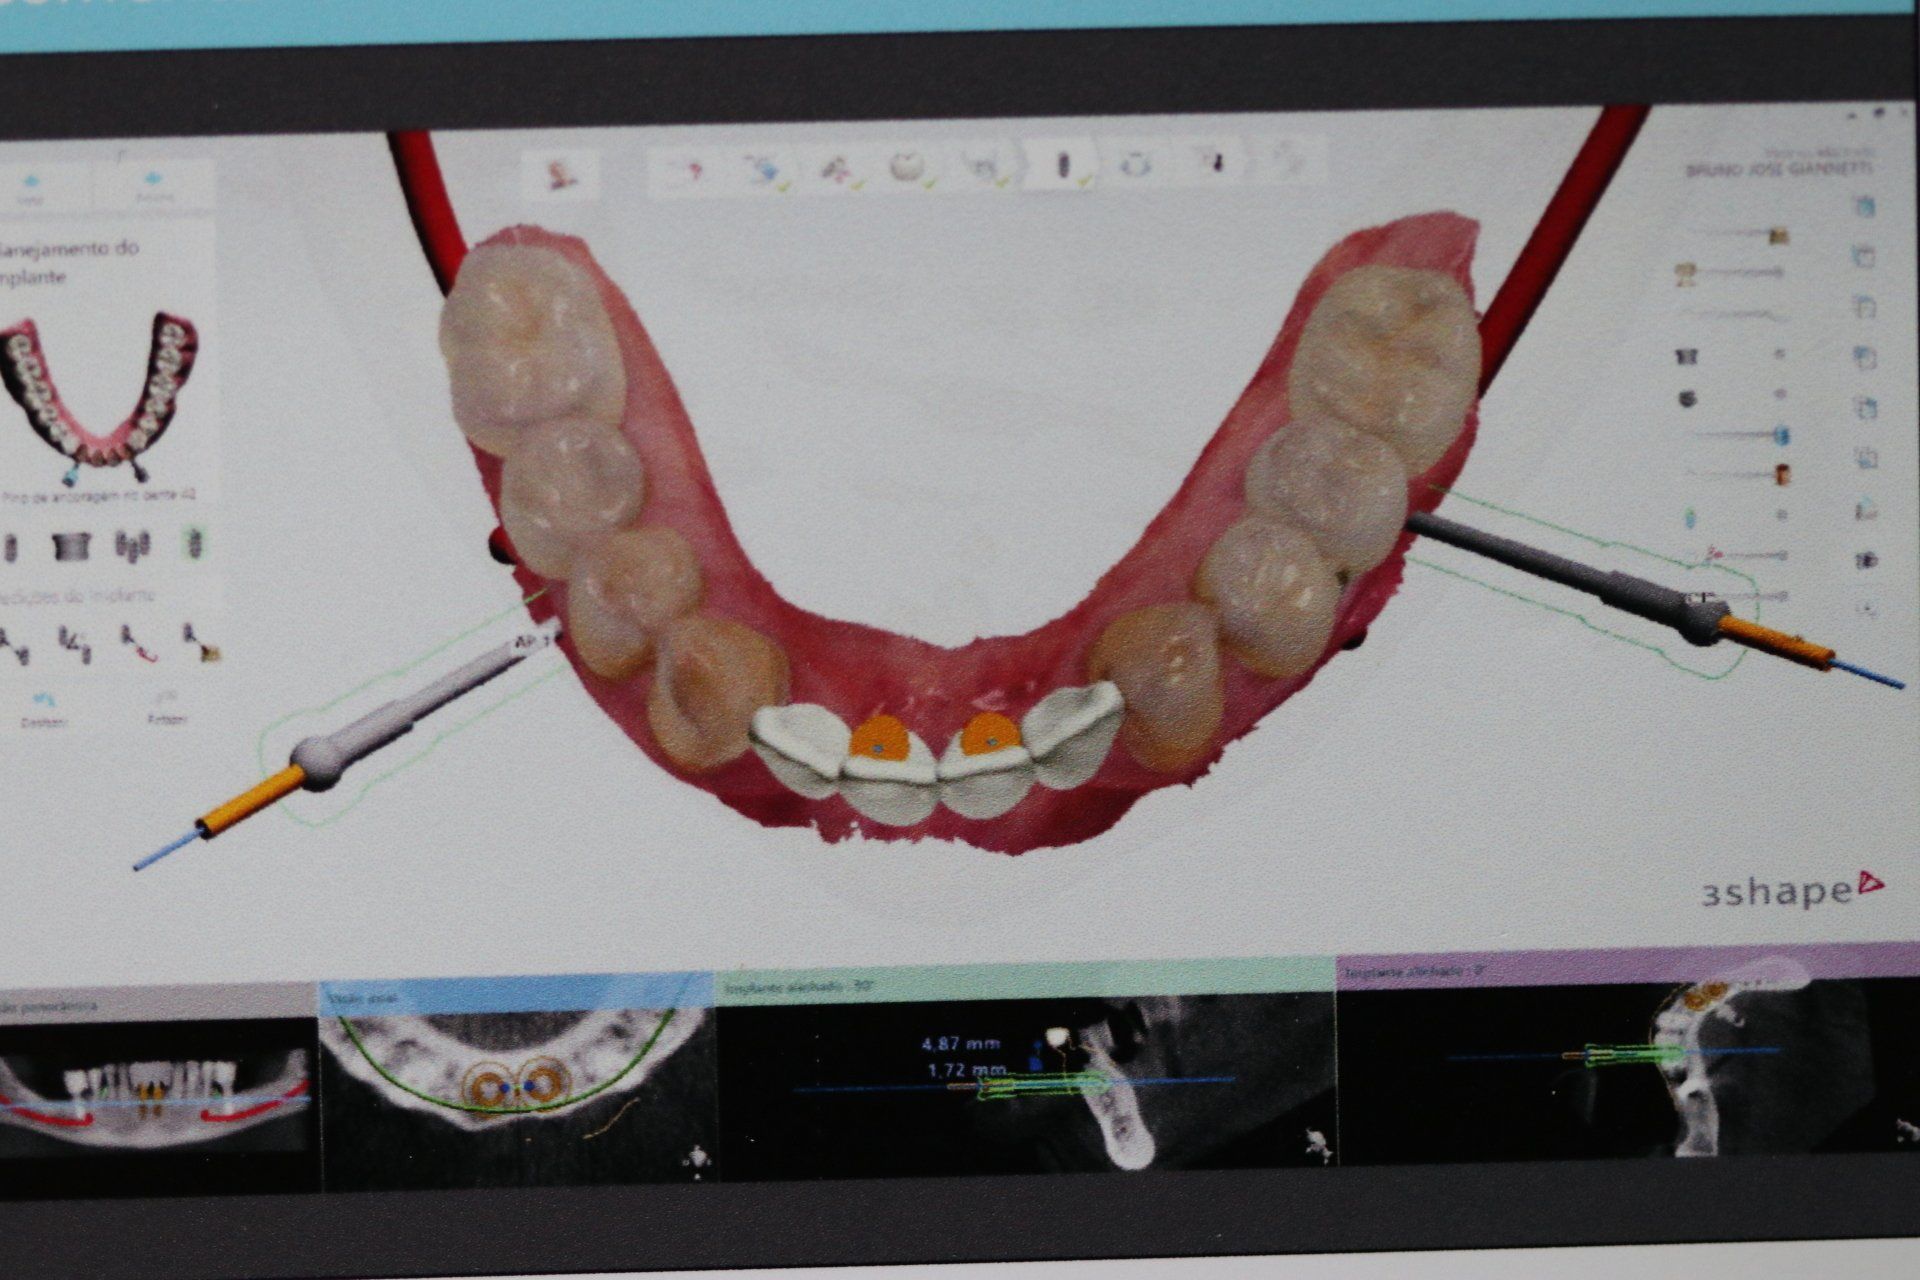

O Implante Dental é um tratamento de Odontologia para reposição dos dentes irrecuperáveis por meio de cirurgias e tratamentos ósseo integráveis.

As imagens apresentadas são apenas ilustrativas do que pode ser conseguido com alguns tratamentos odontológicos, não demonstrando garantia de resultados. Cada situação particular exige diagnóstico e planejamento adequados e individualizados.